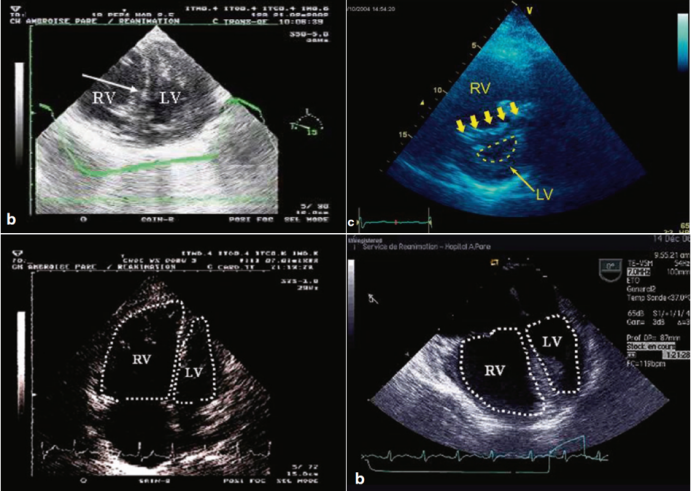

肺栓塞会显著增加右心室后负荷,导致右心室扩张和功能障碍。与左心室相比,正常成人的右心室较小,且适应于低压、低阻力循环。然而,急性或慢性肺血管阻力升高会引发右心室衰竭。急性肺栓塞超声表现为右心室扩张(右心室/左心室比值≥1)、室间隔“D型”变形,伴随收缩末期室间隔运动异常(图2)

图片

2  肺栓塞肺超声表现

除了上述征象,肺栓塞(急性肺心病)还有其他超声表现:①三尖瓣环收缩期位移(TAPSE)缩小,静脉回流梯度减少(<16 mm,提示右室收缩功能降低)。TAPSE测量方法:M型超声,四腔心切面测量三尖瓣环从舒张末期到收缩末期的纵向位移(图3);正常值≥17 mm。②下腔静脉扩张且吸气时无塌陷(提示右心负荷过重)。③右心室腔内直接探及血栓(特异性高)。